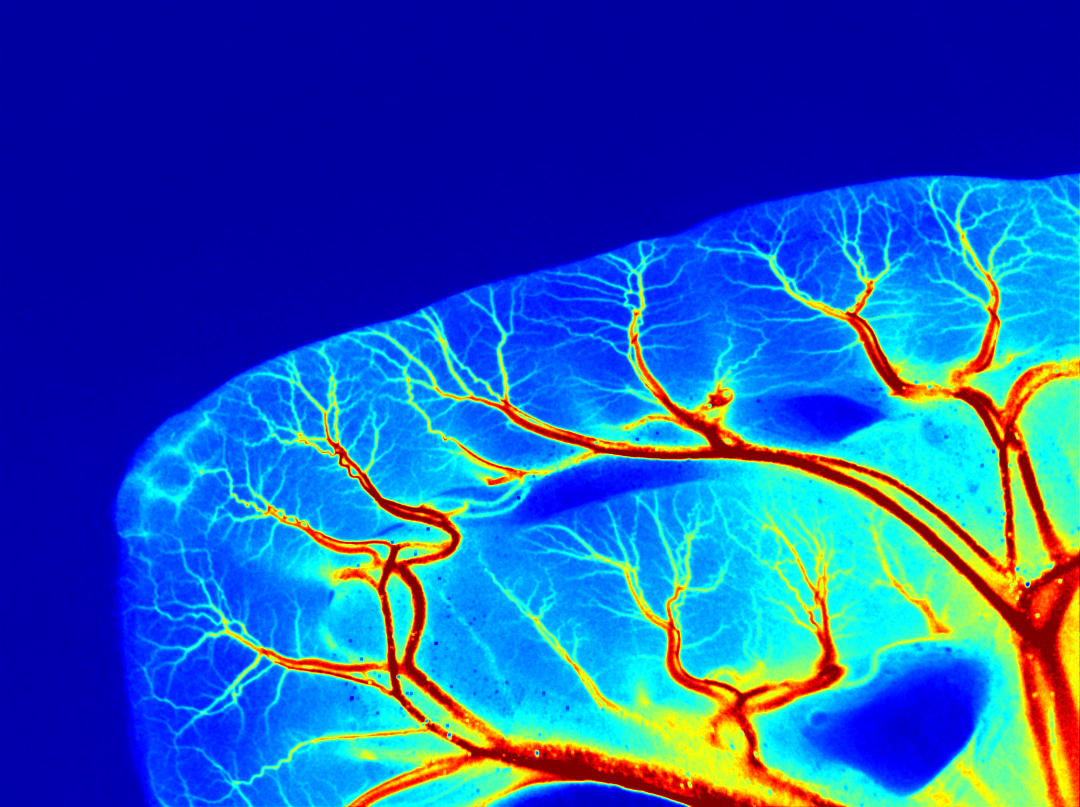

图7.瑞沃德激光散斑血流成像系统成像效果

瑞沃德激光散斑血流成像系统,基于LSCI技术设计,具有高分辨率、非接触式、非侵入性等优势,可实时监测、并直观地呈现活体器官组织微循环血流灌注量分布情况,目前已服务全球150+用户,助力科研人员在Gut、Circulation Research、Blood、Diabetes、theranostics、Nature Communications等业专期刊表发重要究研成果60多篇。

首次亮相SfN的瑞沃德全自动脑立体定位仪,可以通过电脑软件精确控制操作臂移动,软件内置大小鼠脑图谱能更方便、更直观的进行脑立体定位,被国内外客户广为称赞;作为明星产品的激光散斑血流成像系统,可以快速获取高分辨率图片、数据、视频等多维度的结果,助力客户获取客观量化微循环血流量数据,能有效提高实验效率。